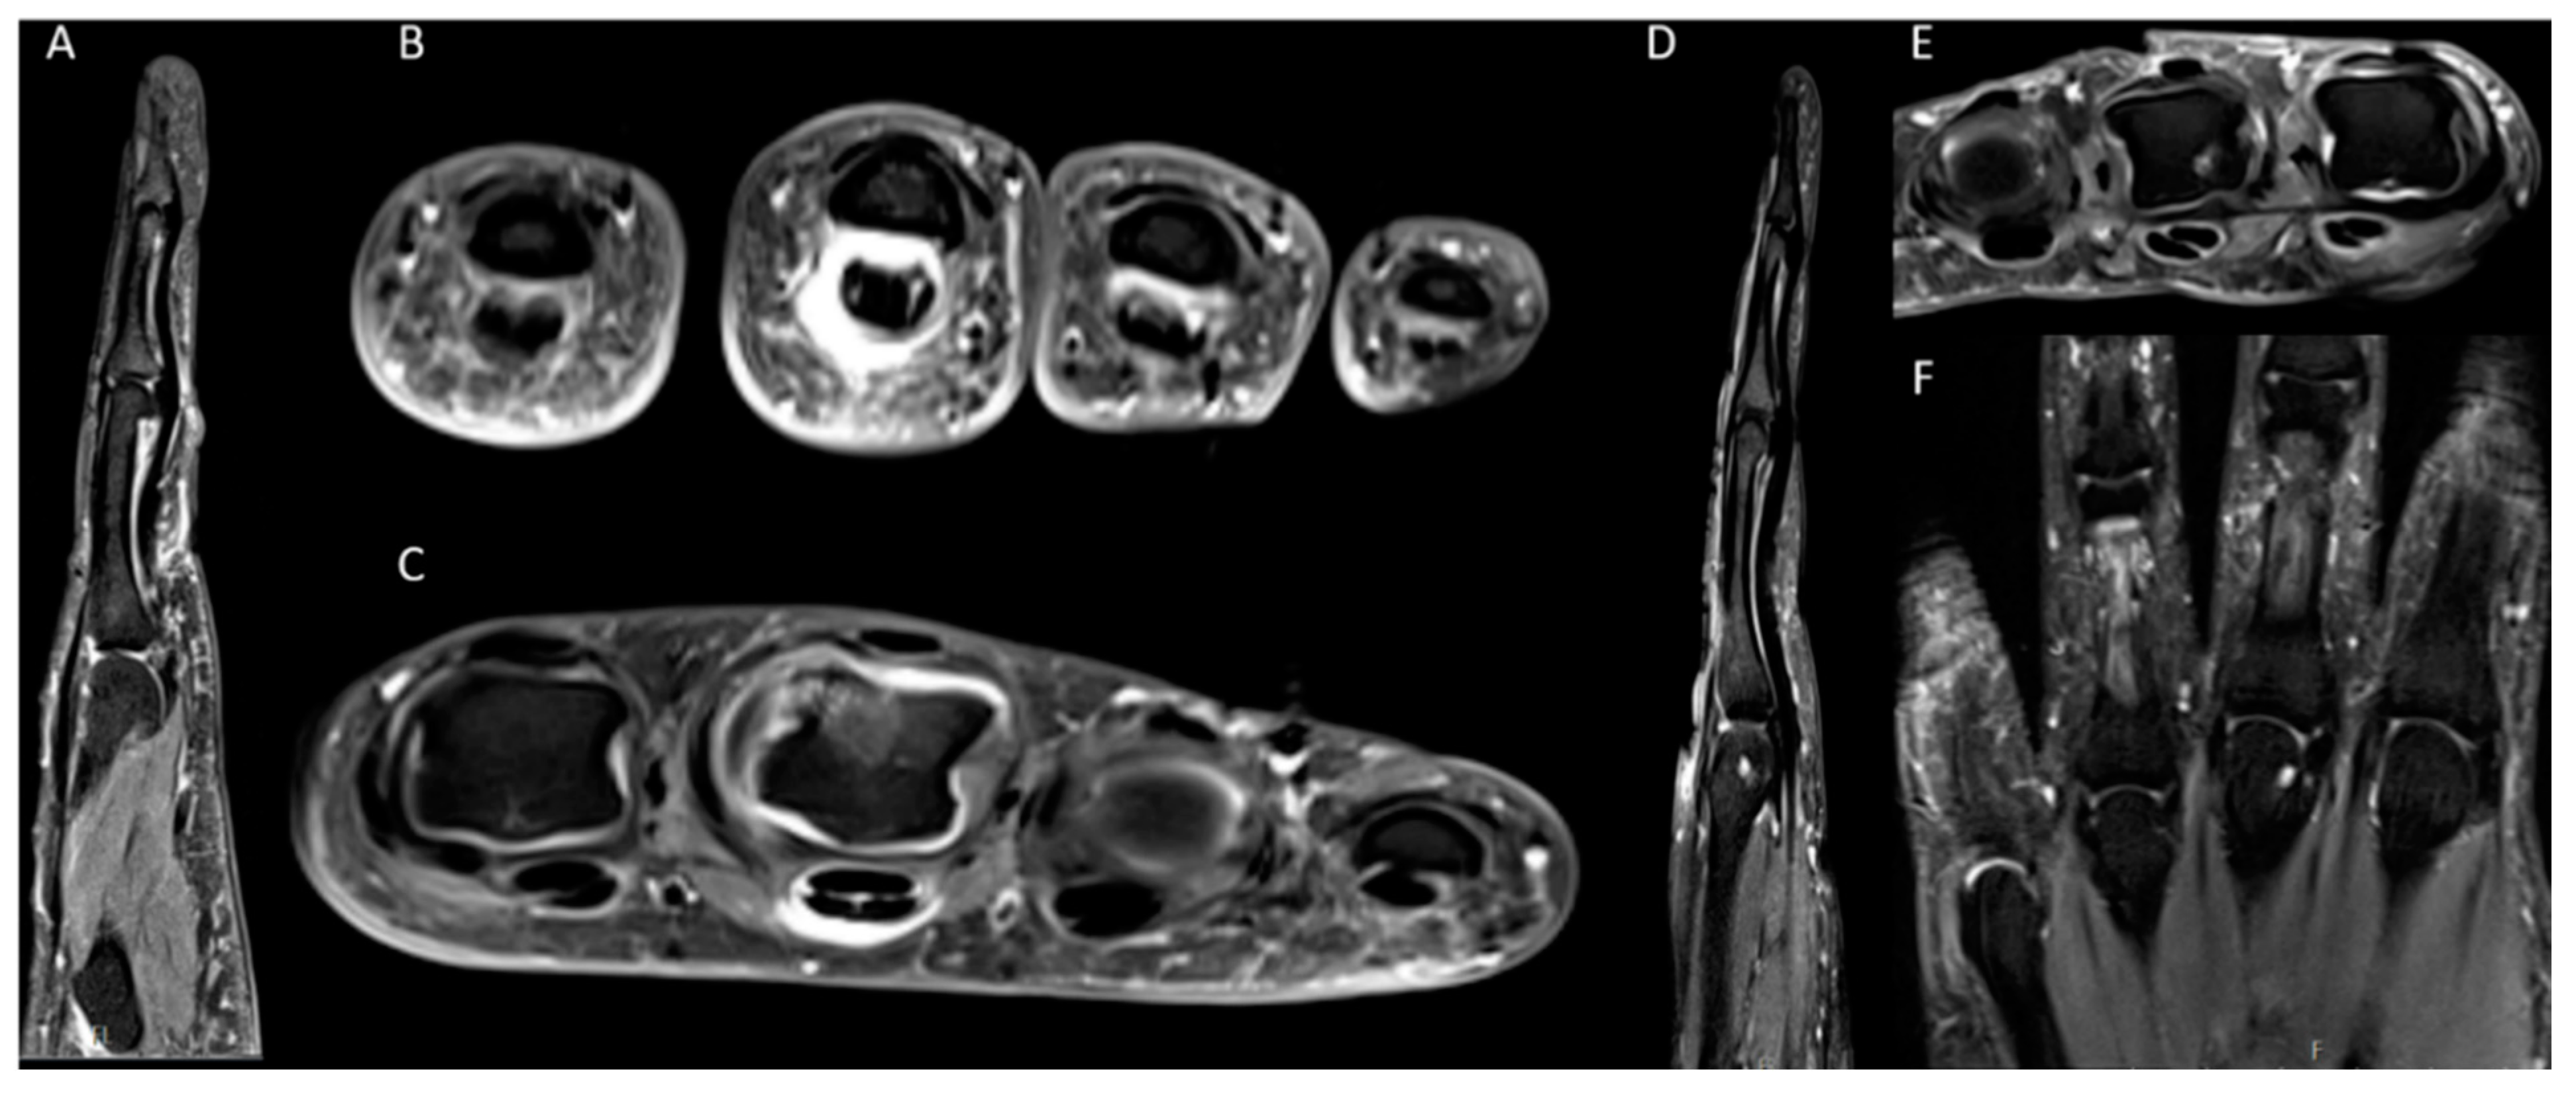

2.2. MRI

2.3. Image Analysis